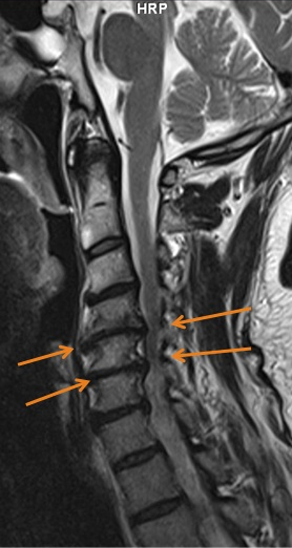

Kernspintomographie (MRT): Bandscheibenvorfall in der Halswirbelsäule

Kernspintomographie (MRT): Knöcherne Stenose in der Halswirbelsäule